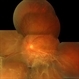

- 70-year-old white female, III CMV, 20/40: OK; 5/200: infilesatire, vasculitis viluitis.